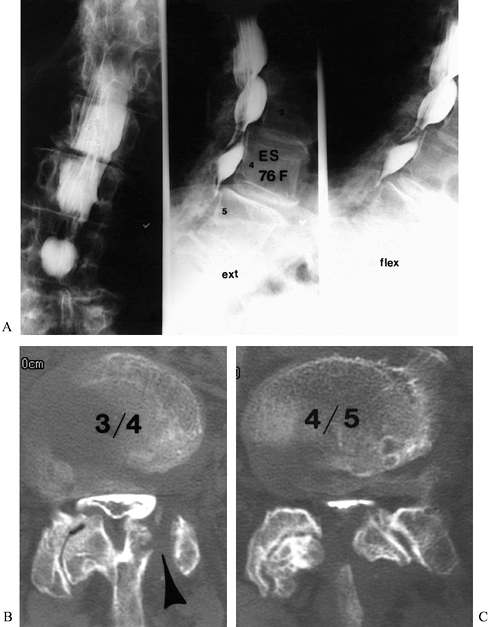

which may reveal the extent of the laminectomy defect, the level of the

previous operation, changes consistent with spinal stenosis, and

evidence of instability on dynamic films. Perform plain films and

dynamic films with the patient standing (weight bearing). Assess any

evidence of abnormal motion, progressive deformity, or progressive

anterolisthesis (Fig. 149.1). Plain radiographs, including

![]() |

Figure 149.1.

A 49-year-old woman approximately 1 year after a decompressive laminectomy, with worsening low-back pain and recurrent leg pain. A: The AP view demonstrates the extent of the laminectomy defect (arrows). B: On the lateral view, subluxation of L-3 on L-4, not present before surgery, is seen, demonstrating postlaminectomy instability. |